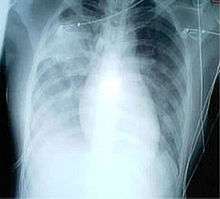

For a case to be considered probable, a chest X-ray must be positive for atypical pneumonia or respiratory distress syndrome.

When it comes to the chest X-ray the appearance of SARS is not always uniform but generally appears as an abnormality with patchy infiltrates.[5]